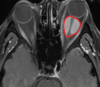

Orbital hemangiopericytoma